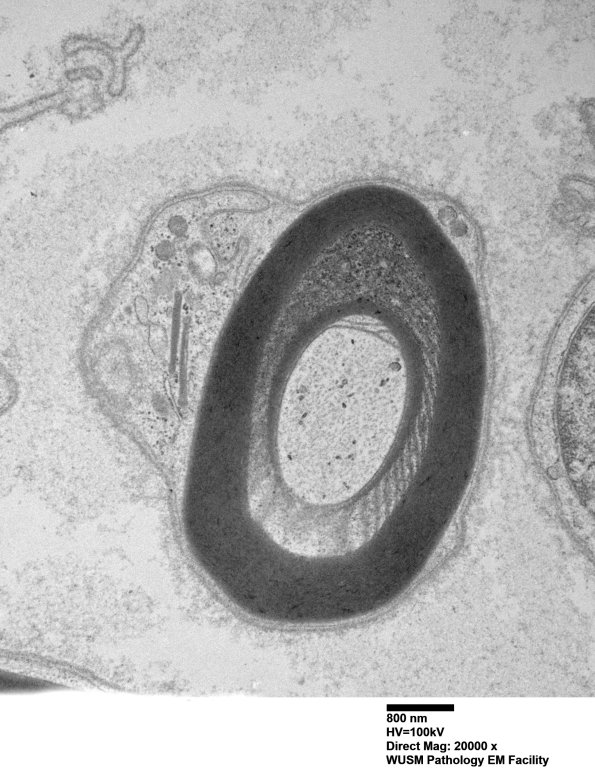

Similar changes surrounded by intact myelin on both sides. (electron micrograph)